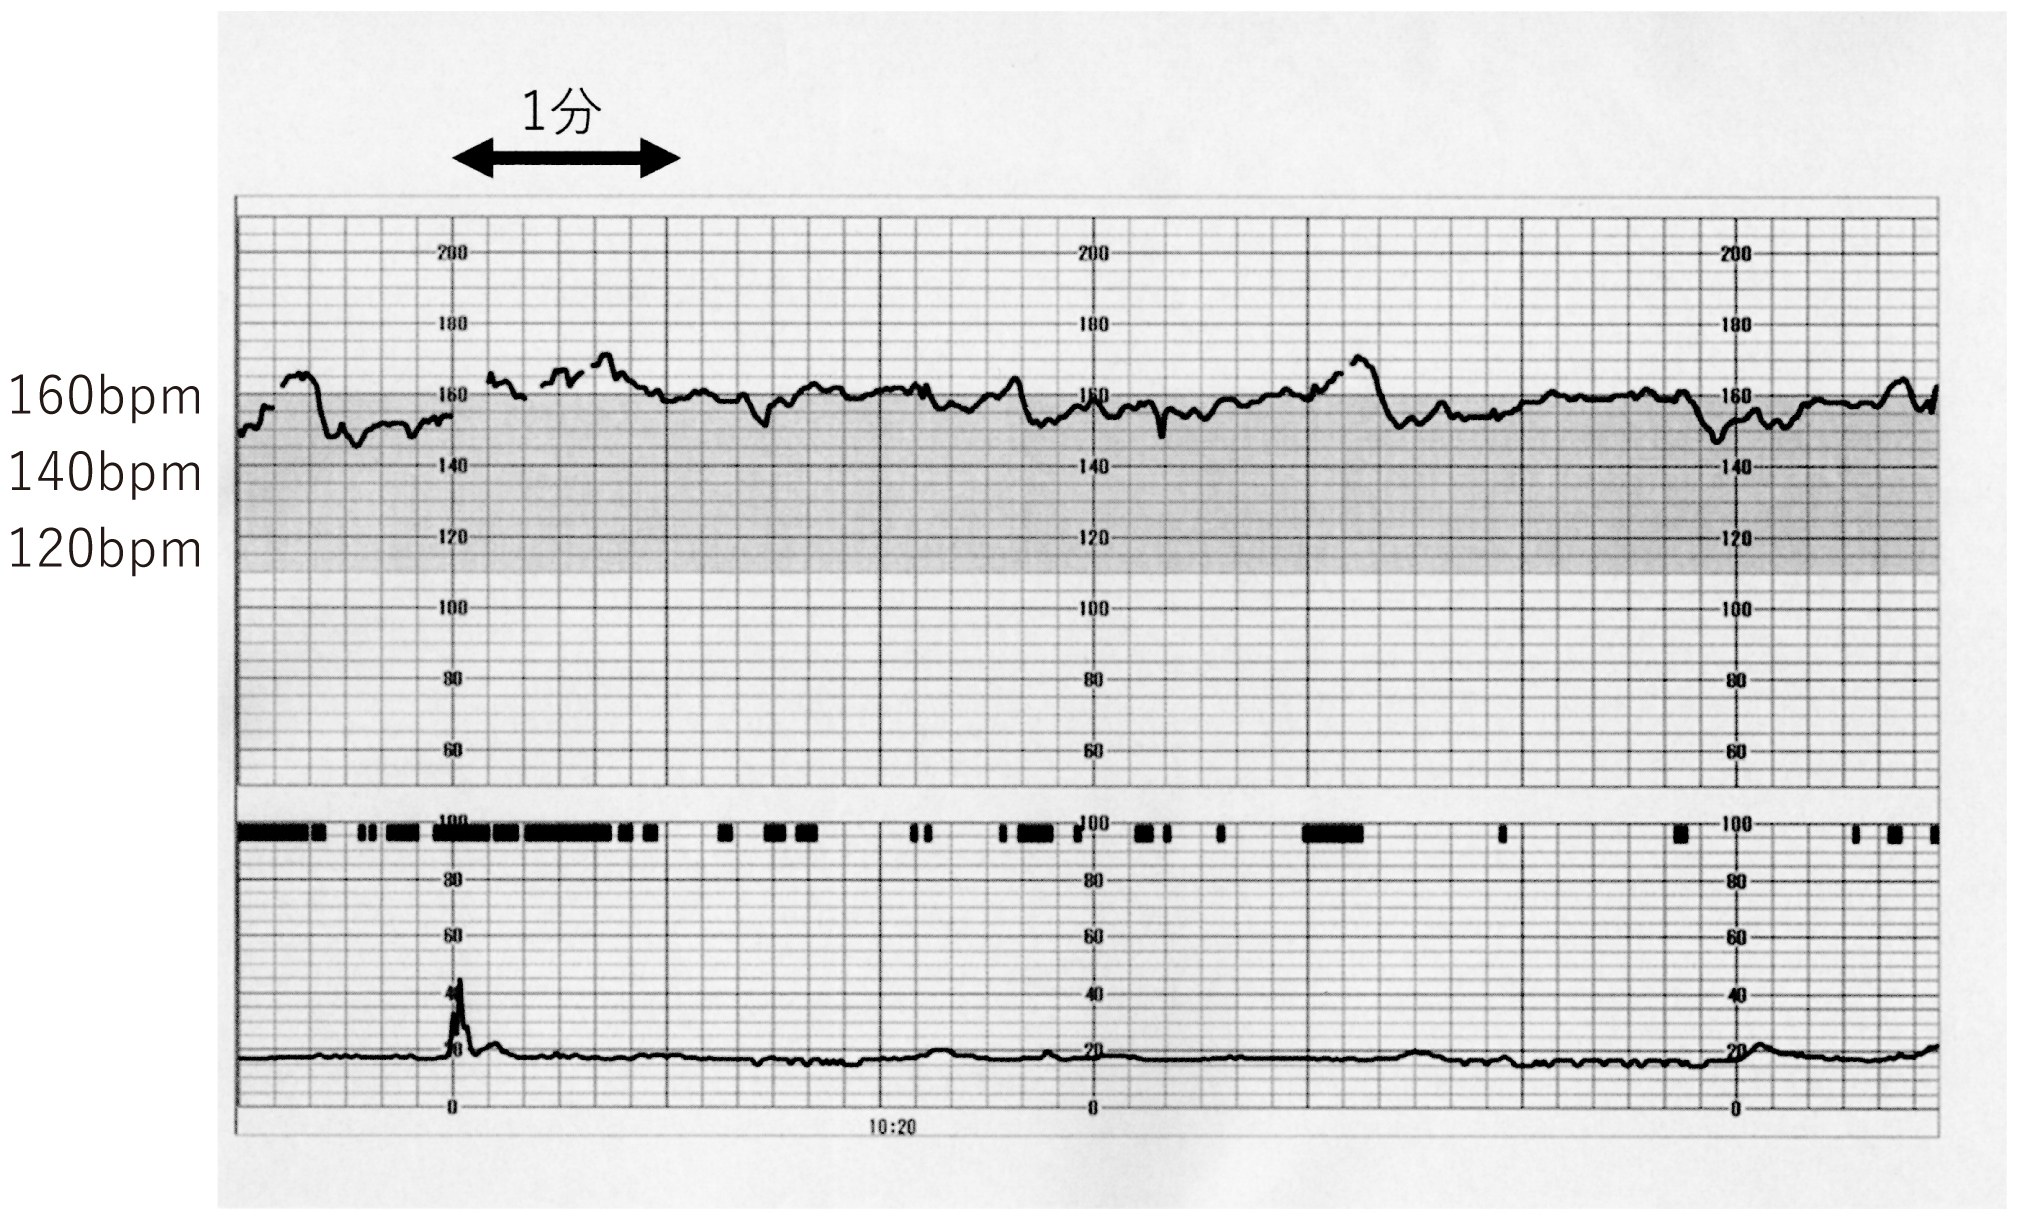

37歳の初妊婦(1妊0産)。妊娠30週,羊水過多の精査目的で紹介受診した。既往歴に特記すべきことはない。妊娠初期・中期の血液検査は異常を認めず,妊娠24週に行われた50g経口ブドウ糖負荷試験は125mg/dL(基準140未満)であった。胎児心拍数陣痛図を下に示す。腹部超音波検査では,胎児発育は正常で,羊水指数〈AFI〉28cm(基準5~24)。胎児に明らかな形態異常はない。